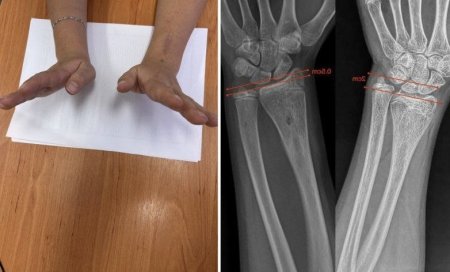

У Закарпатській обласній дитячій лікарні медики застосували сучасну малотравматичну методику, щоб усунути післятравматичну деформацію кісток у 12-річної дівчинки, яка приїхала на лікування з іншої області.

Під час обстеження лікарі виявили, що ріст кістки був порушений через утворення кісткового мостика. Він блокував нормальний розвиток і спричиняв деформацію передпліччя. Ортопеди виконали операцію з видалення цього утворення, що дозволило відновити природній ріст кісткової тканини.

Через сім місяців після втручання передпліччя пацієнтки повністю відновило форму, ріст кістки нормалізувався, а рухливість руки залишилася в повному обсязі.